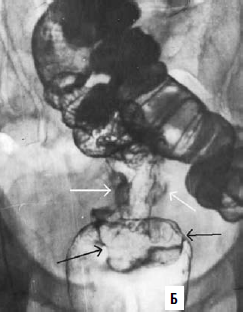

Ирригоскопия – рентгенологическое исследование толстой кишки, производимое с помощью контрастной клизмы. В настоящее время применяют методику дозированного прерывистого заполнения кишки с периодической эвакуацией избыточной контрастной взвеси и двойным контрастированием (раздувание кишки после ее опорожнения).

Рис. 210. Ирригограммы прямой кишки: А – внутрипросветное образование диаметром около 3 см, с бугристым внутренним контуром и втяжением стенки кишки в основании его (черная стрелка) – полиповидный рак прямой кишки; Б – циркулярное сужение верхнеампулярного отдела прямой кишки с бугристыми контурами (белые стрелки), протяженностью около 5 см. У нижнего полюса сужения выявляется выраженный симптом «воротничка» (черные стрелки) – циркулярный рак прямой кишки

Методика заключается в следующем: на первом этапе дозированно, под минимальным давлением заполняется прямая и дистальный отдел сигмовидной кишки, производится изучение состояния стенок при различной степени заполнения. Взвесь частично эвакуируется и производится нагнетание воздуха. Непосредственно после этого контрастируются и исследуются вышележащие отделы ободочной кишки. После опорожнения кишки выполняются рентгенограммы рельефа кишки. Изменяют положение больного. Пациент ложится на живот, при этом в прямую кишку возвращается воздух из проксимальных отделов, и на рентгенограмме прямая кишка видна в условиях умеренного раздувания (двойное контрастирование). Ирригоскопия позволяет выявить следующие признаки: 1) дефект или обрыв складок слизистой, 2) ригидность стенки кишки, 3) дефект заполнения кишки с неровными контурами или нишей, 4) циркулярный стенозирующий дефект или трубчатое сужение кишки на том или ином ее участке, 5) расширение просвета кишки выше суженной области (рис. 210).